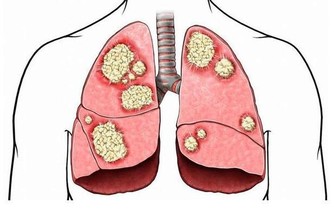

3.腸道

有400多種細菌寄居在腸道之中。腸道內的大腸埃希氏菌是人體客棧中的好房客,

它幫助我們消化,而且也是我們防禦系統的一個組成部分。

但在腸道之外的大腸埃希氏菌卻能致病。

對策:要想保護腸道,建議每天喝1—2瓶酸奶,

其中的益生菌可抑制壞菌群在腸道稱霸,幫助好菌群獲得對腸道的操控權。

另外,堅持適度鍛煉,常做俯臥撑、揉腹等,可防止腸道老化。